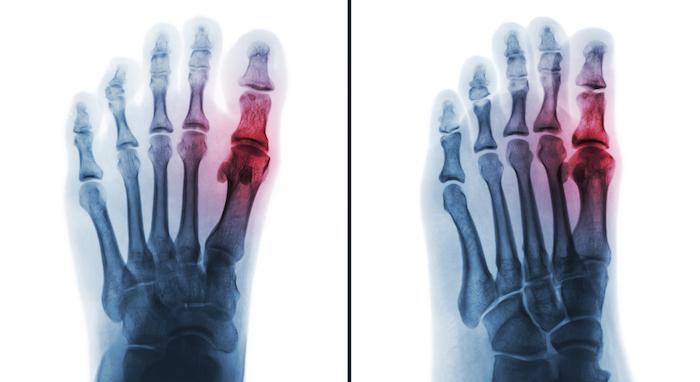

Menée chez plus de 6 000 malades souffrant de goutte, l'étude randomisée a comparé le fébuxostat et l'allopurinol et met en évidence une sur-mortalité cardiaque dans le groupe fébuxostat. Les résultats ont été publiés dans le New England Journal of Medicine.